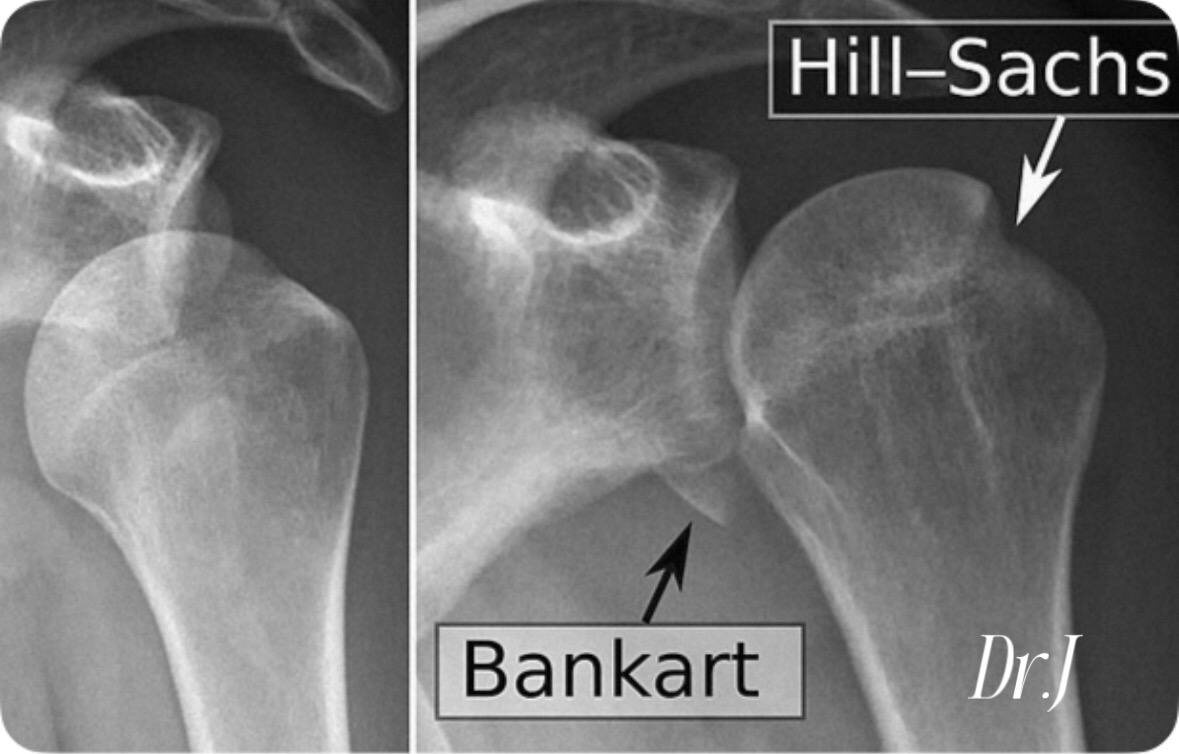

3. Повреждение Банкарта. Отрыв передне-нижней суставной хрящевой губы от впадины лопатки. Возникает в отдалённом периоде после передних вывихов плеча.

Повреждение Хилл-Сакса — это компрессионный перелом или вдавление в задне-верхней части головки плечевой кости, возникающее при переднем вывихе плеча. Это повреждение приводит к нестабильности сустава и увеличивает риск повторных вывихов.